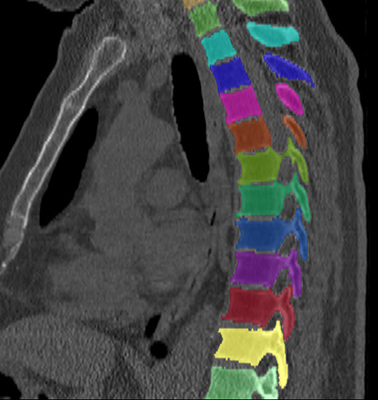

5.1 Segmentation performance

Similar performance was achieved for vertebra segmentation in various CT datasets with an average Dice score of and for vertebral body segmentation in an MR dataset with an average Dice score of . Surface distances were lower on CT images compared to MR images ( vs. ), however, there were also fewer training scans available in the MR dataset. Figure 4 illustrates the magnitude of differences of the automatic segmentations from the ground truth segmentations.

(a) Low-dose chest CT

(b) Lumbar spine CT (xVertSeg.v1 dataset)

(c) Lumbar spine MR

In the CT datasets, the segmentation was more accurate on high-resolution dedicated spine scans of healthy subjects compared with low-dose low-resolution chest CT scans and scans of subjects with in some cases severe compression fractures. This is also visible in the segmentation performance stratified by vertebra (Figure 5). Segmentations were more accurate for the lumbar (L1-L5) than for the thoracic vertebrae (T1-T12), which are covered by the more challenging low-dose chest CT scans. Outliers among the lumbar vertebrae correspond to vertebrae from the xVertSeg.v1 dataset, which features a number of severely deformed lumbar vertebrae that are particularly challenging to segment.

In comparison with other vertebra segmentation methods, our iterative instance segmentation approach outperformed previous methods on the thoracolumbar spine CT dataset as well as on the lumbar spine CT dataset. In both cases, there was a substantial improvement in average Dice score and especially also in the surface distance (Table 1). On the xVertSeg.v1 dataset with various fractured vertebrae, our method performed comparable to the method of Sekuboyina et al. (2017) and not as well as the method of Janssens et al. (2018). However, both of these publications used a different separation between training and evaluation data and the results are therefore not directly comparable. For vertebral body segmentation in MR, our approach achieved on average higher Dice scores and lower surface distances than previous methods, but with higher variance compared to Korez et al. (2016). Although the automatic segmentation was overall accurate on low-dose chest CT, the performance was still slightly below the level of interobserver variation (average difference of in Dice score and in surface distance).